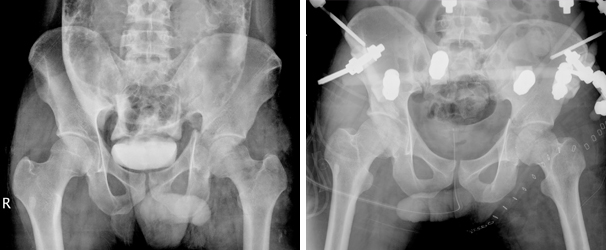

전·후방 비구 골절의 내고정술 전 후방 비구 골절의 내고정술 이미지